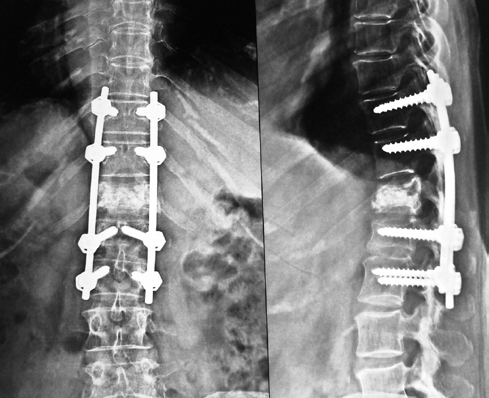

Surgical Treatments of Vertebral Fractures: depends upon the fact that there is only fracture or fracture associated with spinal cord compression. If there is only fracture then cement filling procedure (Vertebroplasty ) is a miraculous procedure under local anesthesia where the patient walks immediately following the surgery. If there is compression of spinal cord leading to weakness in legs then open surgical stabilization with screws is contemplated. Never the less the medical treatment is always to be continued for long. Spinal fixation Vertebroplasy

Multilevel fixation with cement vertebroplasty for osteoporetic fracture non uniting

Percutanious V plasty Percutaneous cement vertebroplasty under local anesthesia. Patient usually walks in 2hrs.